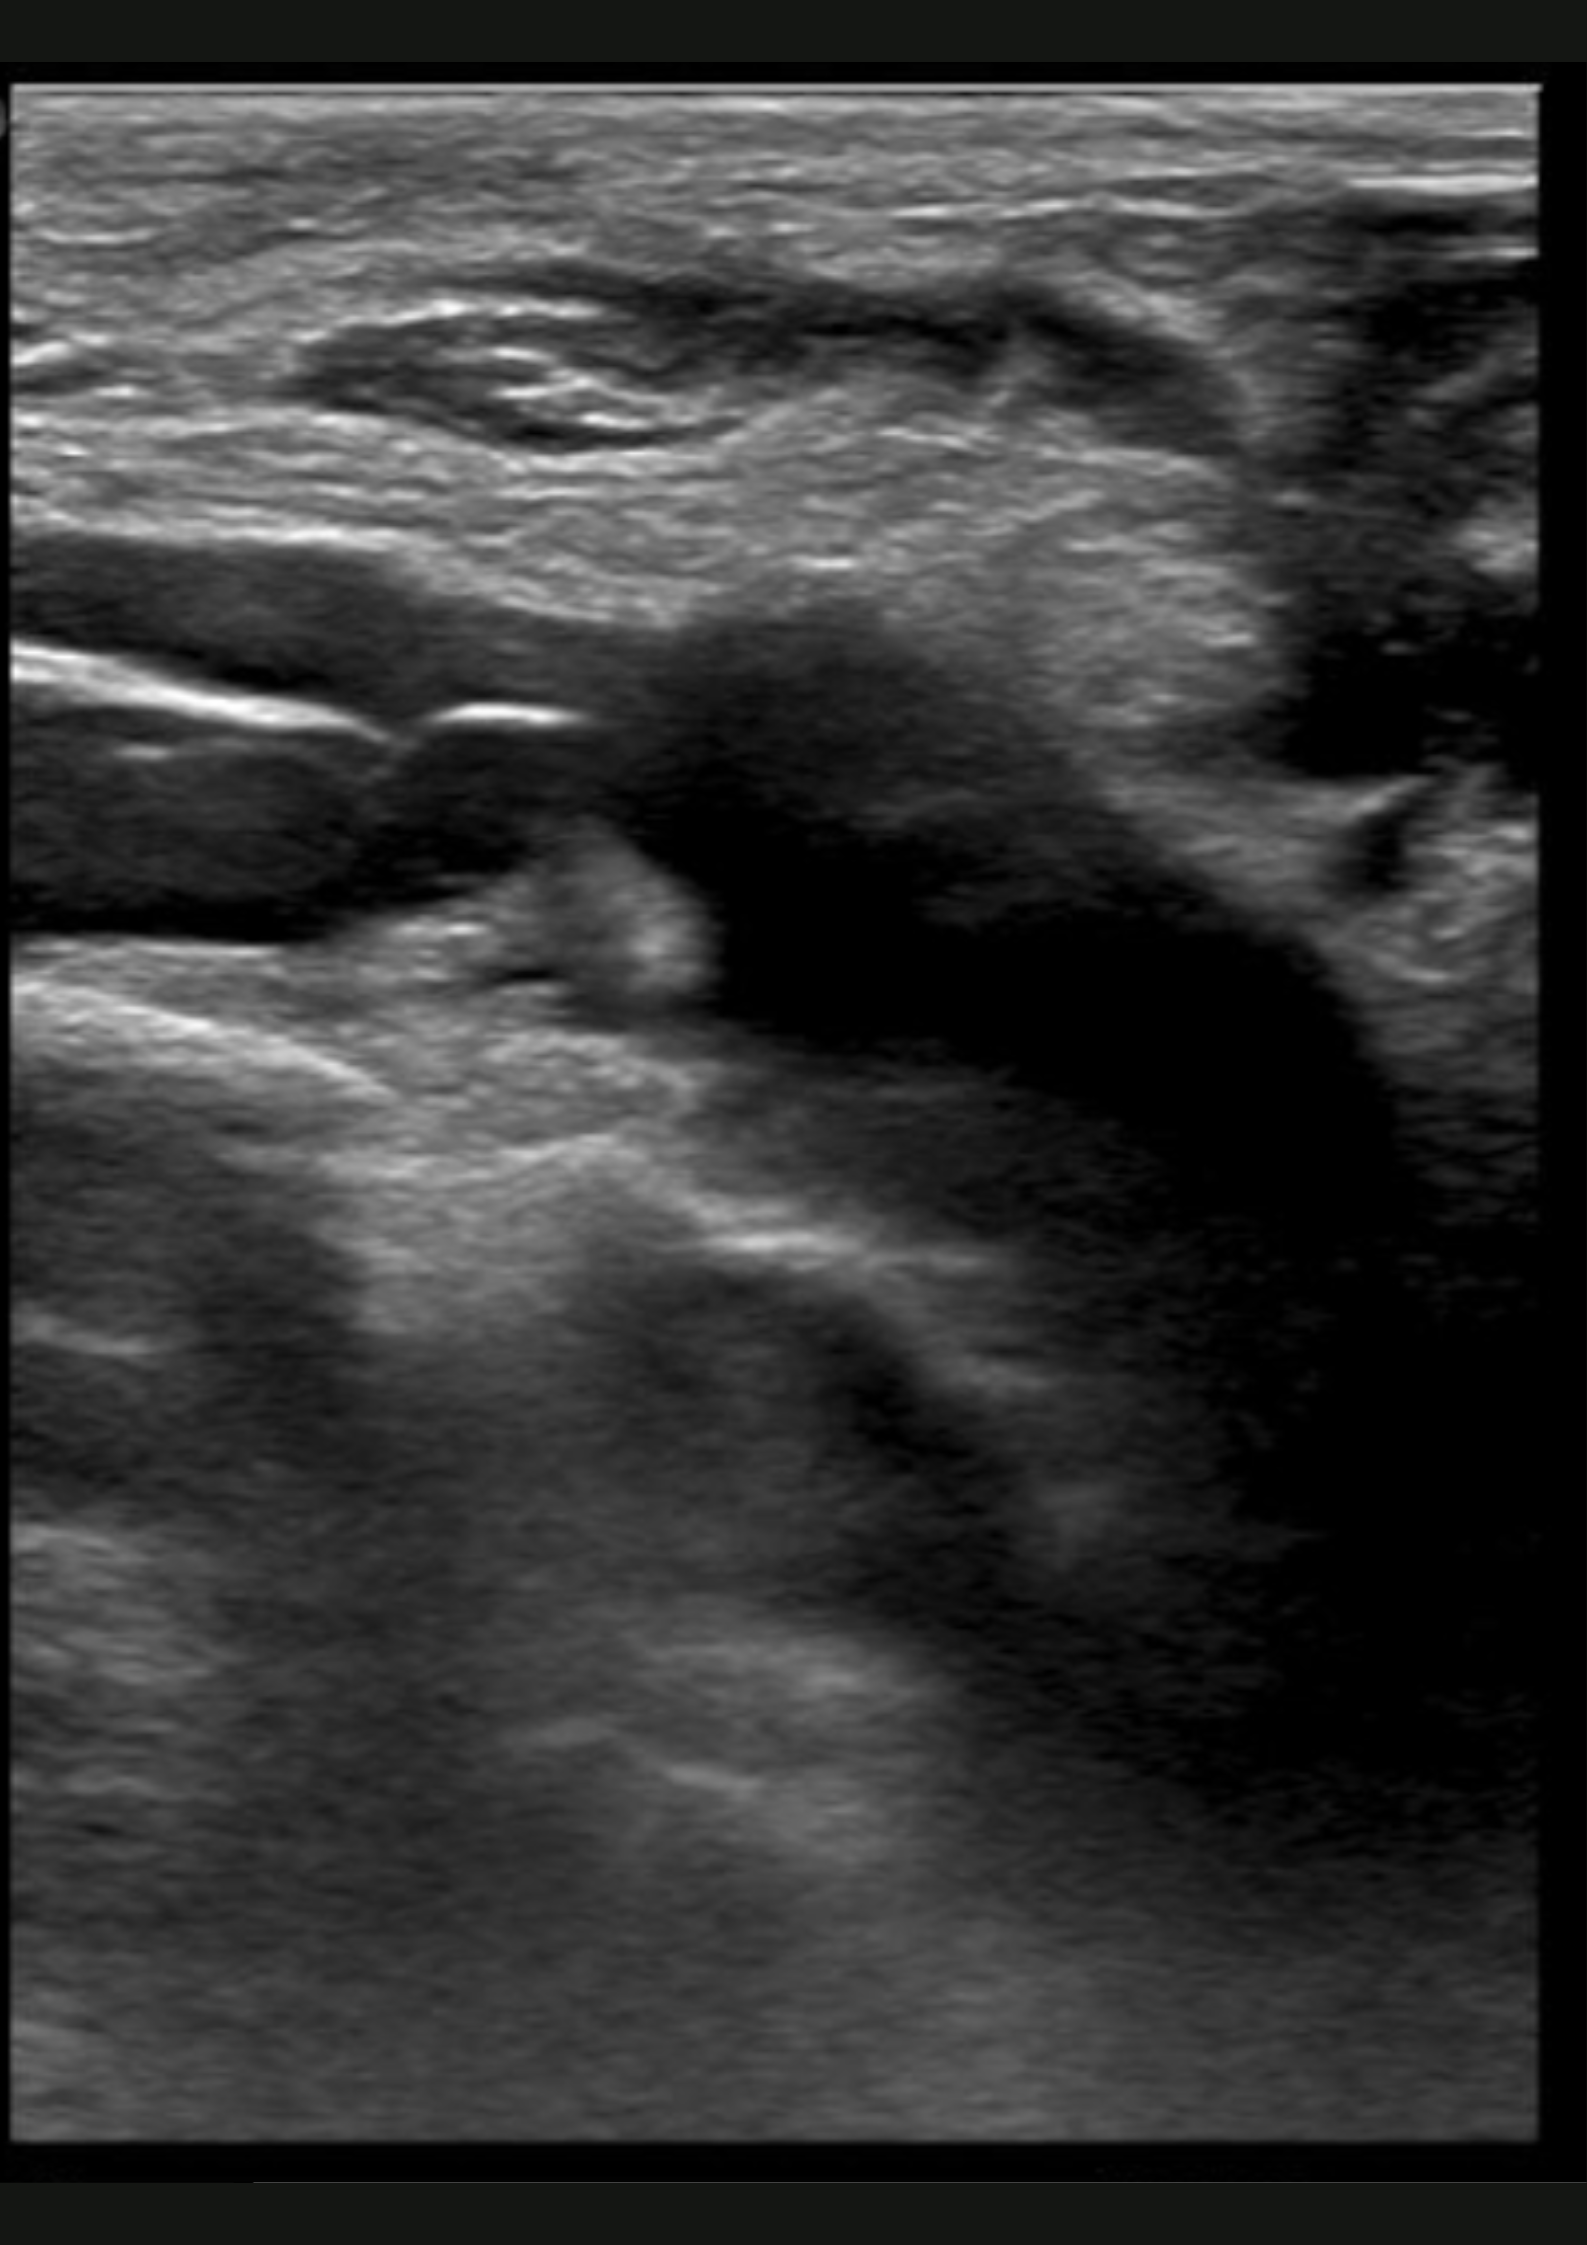

Ante la sospecha de patología muscular sin antecedente traumático, se realiza ecografía.

En la ecografía no apreciamos alteraciones musculares pero observamos dificultad para la compresión de la vena subclavia derecha en extensión.

Trombosis venosa profunda de sublcaiva, innominada, cefálica y yugular derecha.

Se remite a Urgencias del hospital de referencia con hallazgos de coagulación: INR 1.05, fibrinógeno 464, Dímero D 1222; y una ecografía de partes blandas que muestra una trombosis venosa de la vena subclavia derecha y vena innominada, con ligera extensión a la vena yugular derecha y cefálica derecha. Posteriormente, se inicia heparina subcutánea y se realiza fibrinolisis con perfusión de urokinasa. En el estudio de coagulación posterior se determinó una hiperhomocisteinemia y probable síndrome antifosfolípido (Paget-Schroetter).